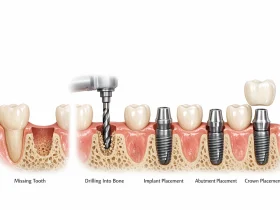

مراحل انجام کامپوزیت دندان

فرآیند انجام کامپوزیت دندان معمولاً ساده و سریع است و در بسیاری از موارد در یک جلسه انجام میشود.

در مرحله اول، دندانپزشک وضعیت دندانها را بررسی میکند تا مطمئن شود این روش برای بیمار مناسب است. در صورت نیاز ممکن است سطح دندان کمی آمادهسازی شود.

در مرحله بعد ماده کامپوزیتی به صورت لایهای روی دندان قرار داده میشود. هر لایه با استفاده از نور مخصوص سخت میشود تا استحکام لازم را پیدا کند.

پس از قرار دادن لایهها، دندانپزشک شکل نهایی دندان را تنظیم میکند تا با سایر دندانها هماهنگ باشد. در نهایت سطح کامپوزیت پولیش میشود تا ظاهری براق و طبیعی ایجاد شود.